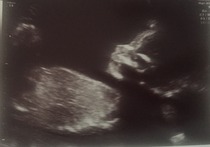

A big relief but for my own peace of mind we decided to book a private scan just to make sure baby was the right size etc...as a bonus it was booked for Mother's Day and we would also find out the gender. Or so we thought! Baby refused to show us, despite the sonographer sending us out for food and rescanning us a couple of hours later, deciding instead to sleep soundly. The company very kindly said they would rescan us again a week later for nothing. Anyway after a lot of moving around, a bit of prodding, our baby consented to reveal his junk Grin and we can't wait to meet our little boy. 18+4 today.

Attached is the 3d scan from last week and scans from yday- the second one shows him taking a big gulp of "delicious" amniotic fluid.

I had my scan this morning and all is well with the wriggly babe! Got some amazingly clear views, saw it kicking around, putting hands behind head and doing a massive yawn which was pretty incredible! Measurements and organs all fine. We are still team yellow...I thought it was a girl at first then I am sure I saw boys bits at one point but who knows, it's still all up in the air! Just delighted its healthy and well. Picture's attached.